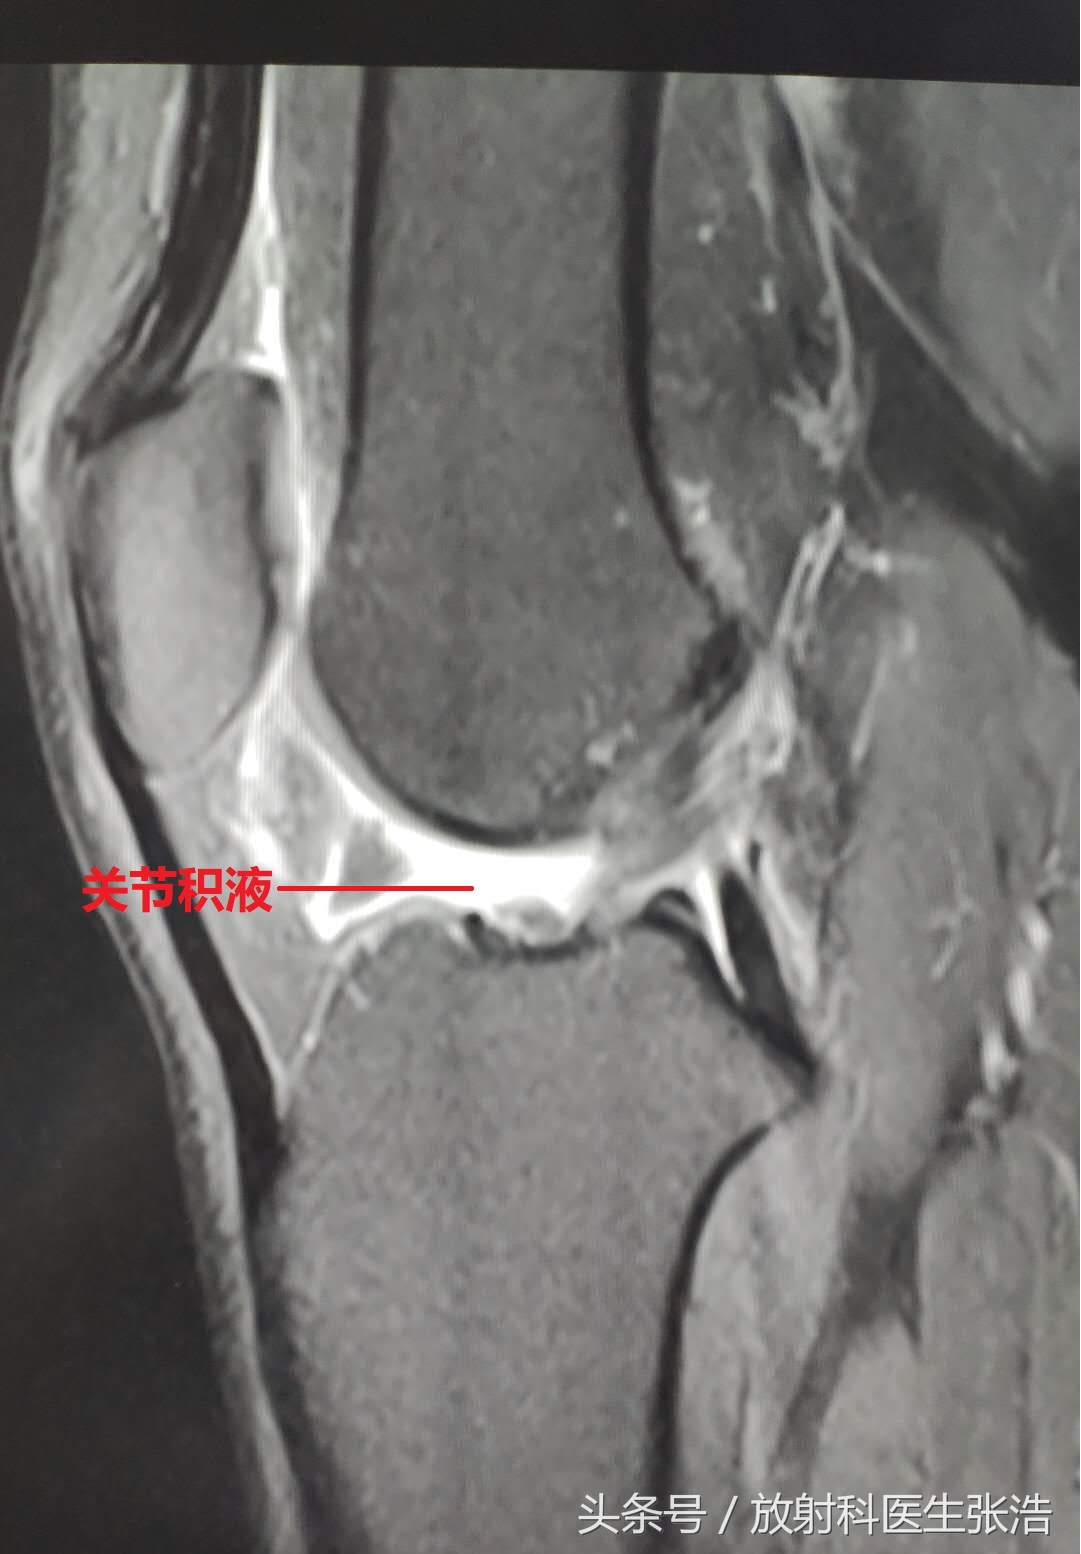

拍了x光片骨头没有问题,但是膝关节任然疼难忍!问题就在软组织结构了!这个时候我们就需要做膝关节的核磁共振检查,这不做不知道,做了结果很多时候真的能吓自己一大跳!我们一起来看看几个膝关节疼痛的患者做完核磁共振的图像结果!

2、第二张我们可以看到在膝关节的关节腔内有很多水样的长T2信号,这就是关节积液了,有些患者关节积液非常多,感觉膝关节特别肿胀,但是拍片又没事,问题就在关节积液,这样一下就找到原因了。